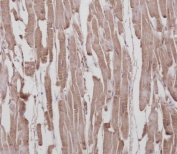

Immunohistochemical analysis of paraffin-embedded human heart section using ROR1 antibody. Ab was diluted at 1:25 dilution.

IHC testing of FFPE human heart tissue with ROR1 antibody at 1:100 dilution. HIER: steamed antigen retrieval with pH9 EDTA buffer.